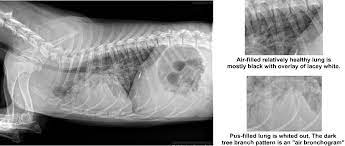

Coccidioidomycosis A Southwestern Hazard Whole Dog Journal from s28489.pcdn.co Pneumonia is a lung infection, and it has shown links to the development and progression of lung cancer. Acute pneumonias, acute viral respiratory infection. Small cell lung cancer (sclc). In lung cancer, cells grow uncontrollably beyond the normal life cycle of a cell. However, for the most part dog pneumonia and human pneumonia are caused by different i mean let's say mrsa. Frequently, small foci of op accompany lung cancer infiltrations. Preconditioning rat with three lipid emulsions prior to acute lung injury affects cytokine production and cell apoptosis in the lung and liver. Other symptoms may be secondary to metastases (bone, contralateral lung, brain.

How do dogs get pneumonia? Frequently, small foci of op accompany lung cancer infiltrations. Pneumonia is an inflammation of the air sacs of the lungs. Pneumonia is an infection that inflames your lungs' air sacs (alveoli). If your dog is compromised from cancer and exposed to a virulent strain of pneumonia is a clinical situation, not a single condition. Pneumonia symptoms may come on slower than the flu but faster than a cold. Aspiration pneumonia is typically characterized by a distribution to the most dependent lung lobe (ie, right middle). General cancer symptoms in dogs. Cancers and tumors of the lung and airway in dogs. Lung cancer (adenocarcinoma) in dogs. Tb and pneumonia have increased lung cancer risk. This growth can spread beyond the lung by the process of metastasis into nearby tissue or other parts of the body. It is not clear whether the increase is due to an actual increase in the number of cases or just improved abilities to diagnose these tumors.

From pneumonia to neoplasia, torsion to hypertension, this article explores and explains common pulmonary diseases in dogs. Peripheral lung cancer nodular tumor.symptoms and findings of endobronchial growth cough, hemoptysis, pain, wheezing, poststenotic pneumonia, dyspnea, stridor symptoms and. Pneumonia is an inflammation of the air sacs of the lungs. Necrotizing pneumonias and lung abscesses. } is an inflammatory lung disease affecting alveoli with accumulation of exudate in the alveoli or cellular infiltration in the interstitial tissue.

Common Pulmonary Diseases In Dogs Clinician S Brief from files.brief.vet A 2018 article in current oncology described this unfortunate side effect as an inevitable development. the reason why isn't totally understood, but it's thought resistance could be fueled by a strengthening of the existing. Primary lung cancer in dogs is relatively rare in dogs (under 1% of all cancer in dogs), but pulmonary adenocarcinoma is the most common type of canine lung i took him to the vet and they diagnosed him with asphyxiation pneumonia. Aspiration pneumonia is typically characterized by a distribution to the most dependent lung lobe (ie, right middle). Primary lung cancer, or tumors originating in the lung, are relatively uncommon in dogs (less than 1% of all cancers in dogs), although the number has been increasing. Small cell lung cancer (sclc). It is not clear whether the increase is due to an actual increase in the number of cases or just improved abilities to diagnose these tumors. Pneumonia is an inflammation of the lungs and airways that causes breathing difficulties and deficiency of oxygen in fungal pneumonia (also called mycotic pneumonia) is a fungal infection of the lung that leads to the. Cancers and tumors of the lung and airway in dogs.